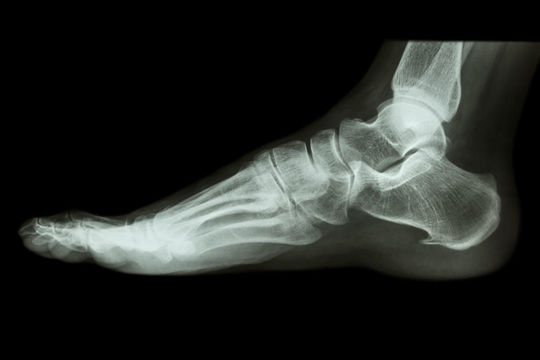

整形外科ではMRIで肩を調べますが「原因はわからなかった」と海莉くんは言います。

神経所見や理学所見も取らず画像検査へ進んでは何も理解は出来ません。

これらの情報から大まかな原因を予測し、最後に画像検査で確認、判断します。

この流れが本来の整形外科の診断です。